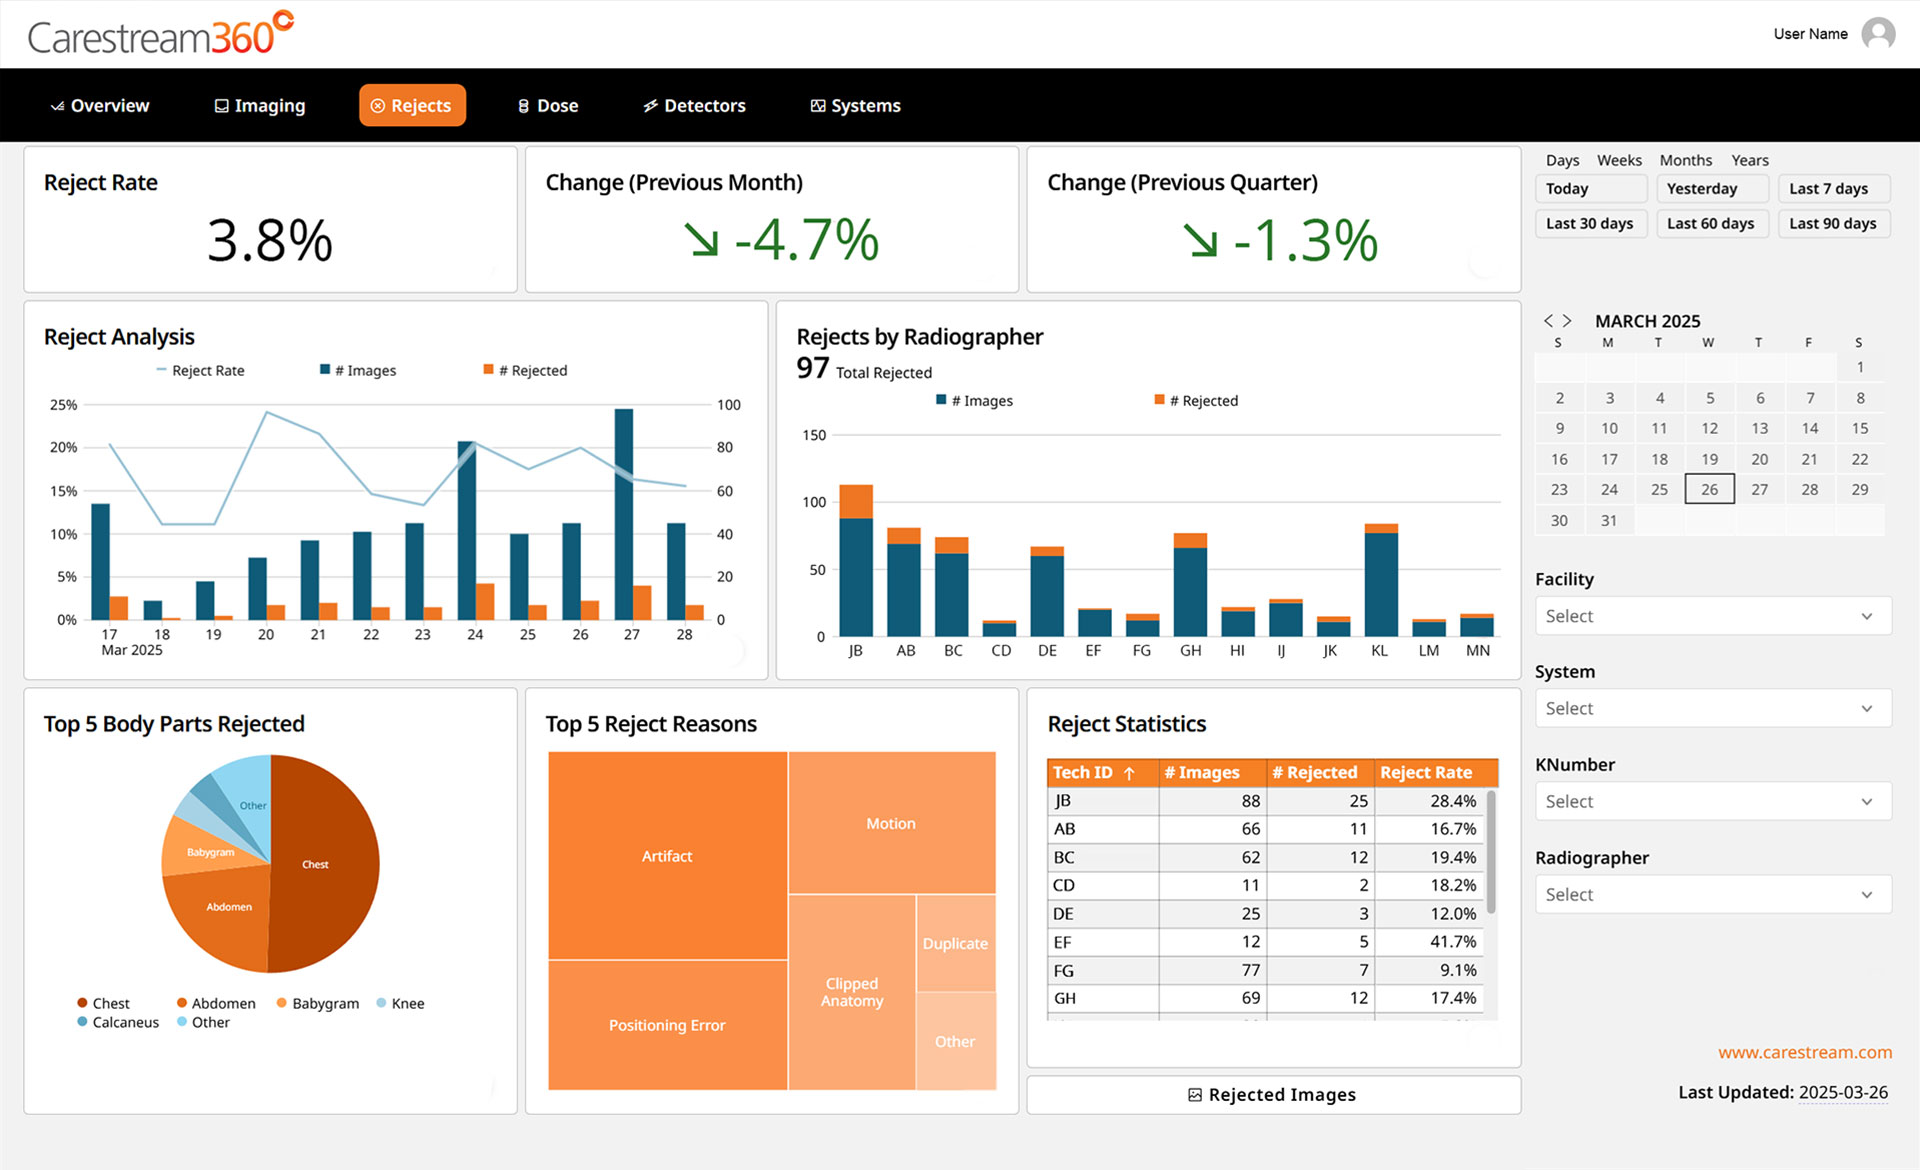

Carestream 360º provides powerful tools to help radiology teams understand, track, and improve image quality through advanced reject analysis.

The Story Behind the Stats

Get direct access to rejected images, enabling visual review that delivers deeper understanding and meaningful insights to guide smarter corrections.

In-Depth Analysis

Clear visuals make trends and problem areas easy to spot so, you can focus your efforts where they’ll have the greatest impact.

Smarter Collaboration

Review images and data together, providing a powerful tool for shared learning and collaborative coaching to build skills and enhance image quality.

Automated Reporting

Stay on top of QA with less effort—receive a monthly reject analysis report automatically by email, giving you the insights you need without the manual work. More time for improvement, less time chasing data.